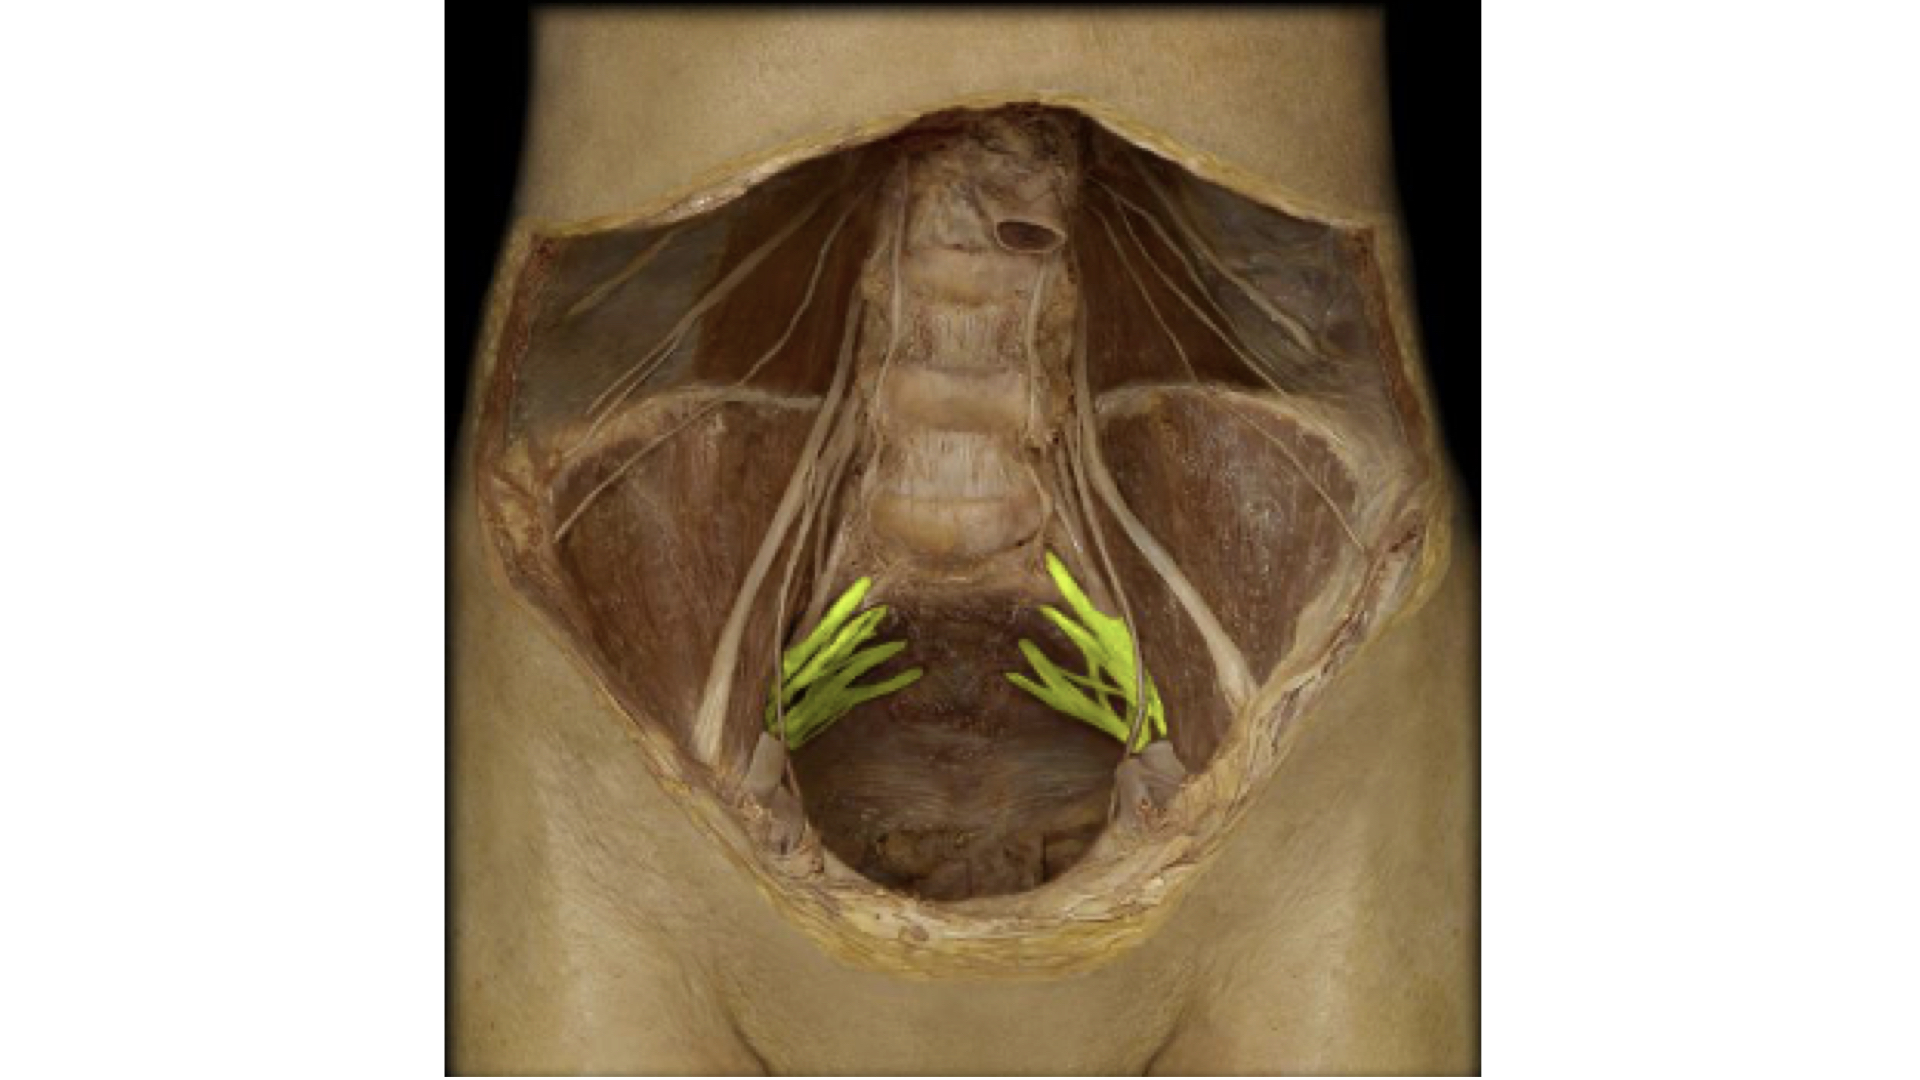

e. Sacral/Coccygeal Plexus: The primary nerve from this plexus is the sciatic nerve.

Sacral/Coccygeal Plexus with Nerves forming the Sciatic Nerve Highlighted

Sacral/Coccygeal Plexus with Nerves forming the Sciatic Nerve Highlighted